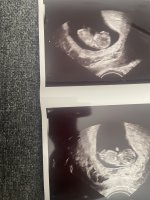

hjertet banket og vi fikk til og med et lite hopp. Målte helt riktig til hvor langt jeg var